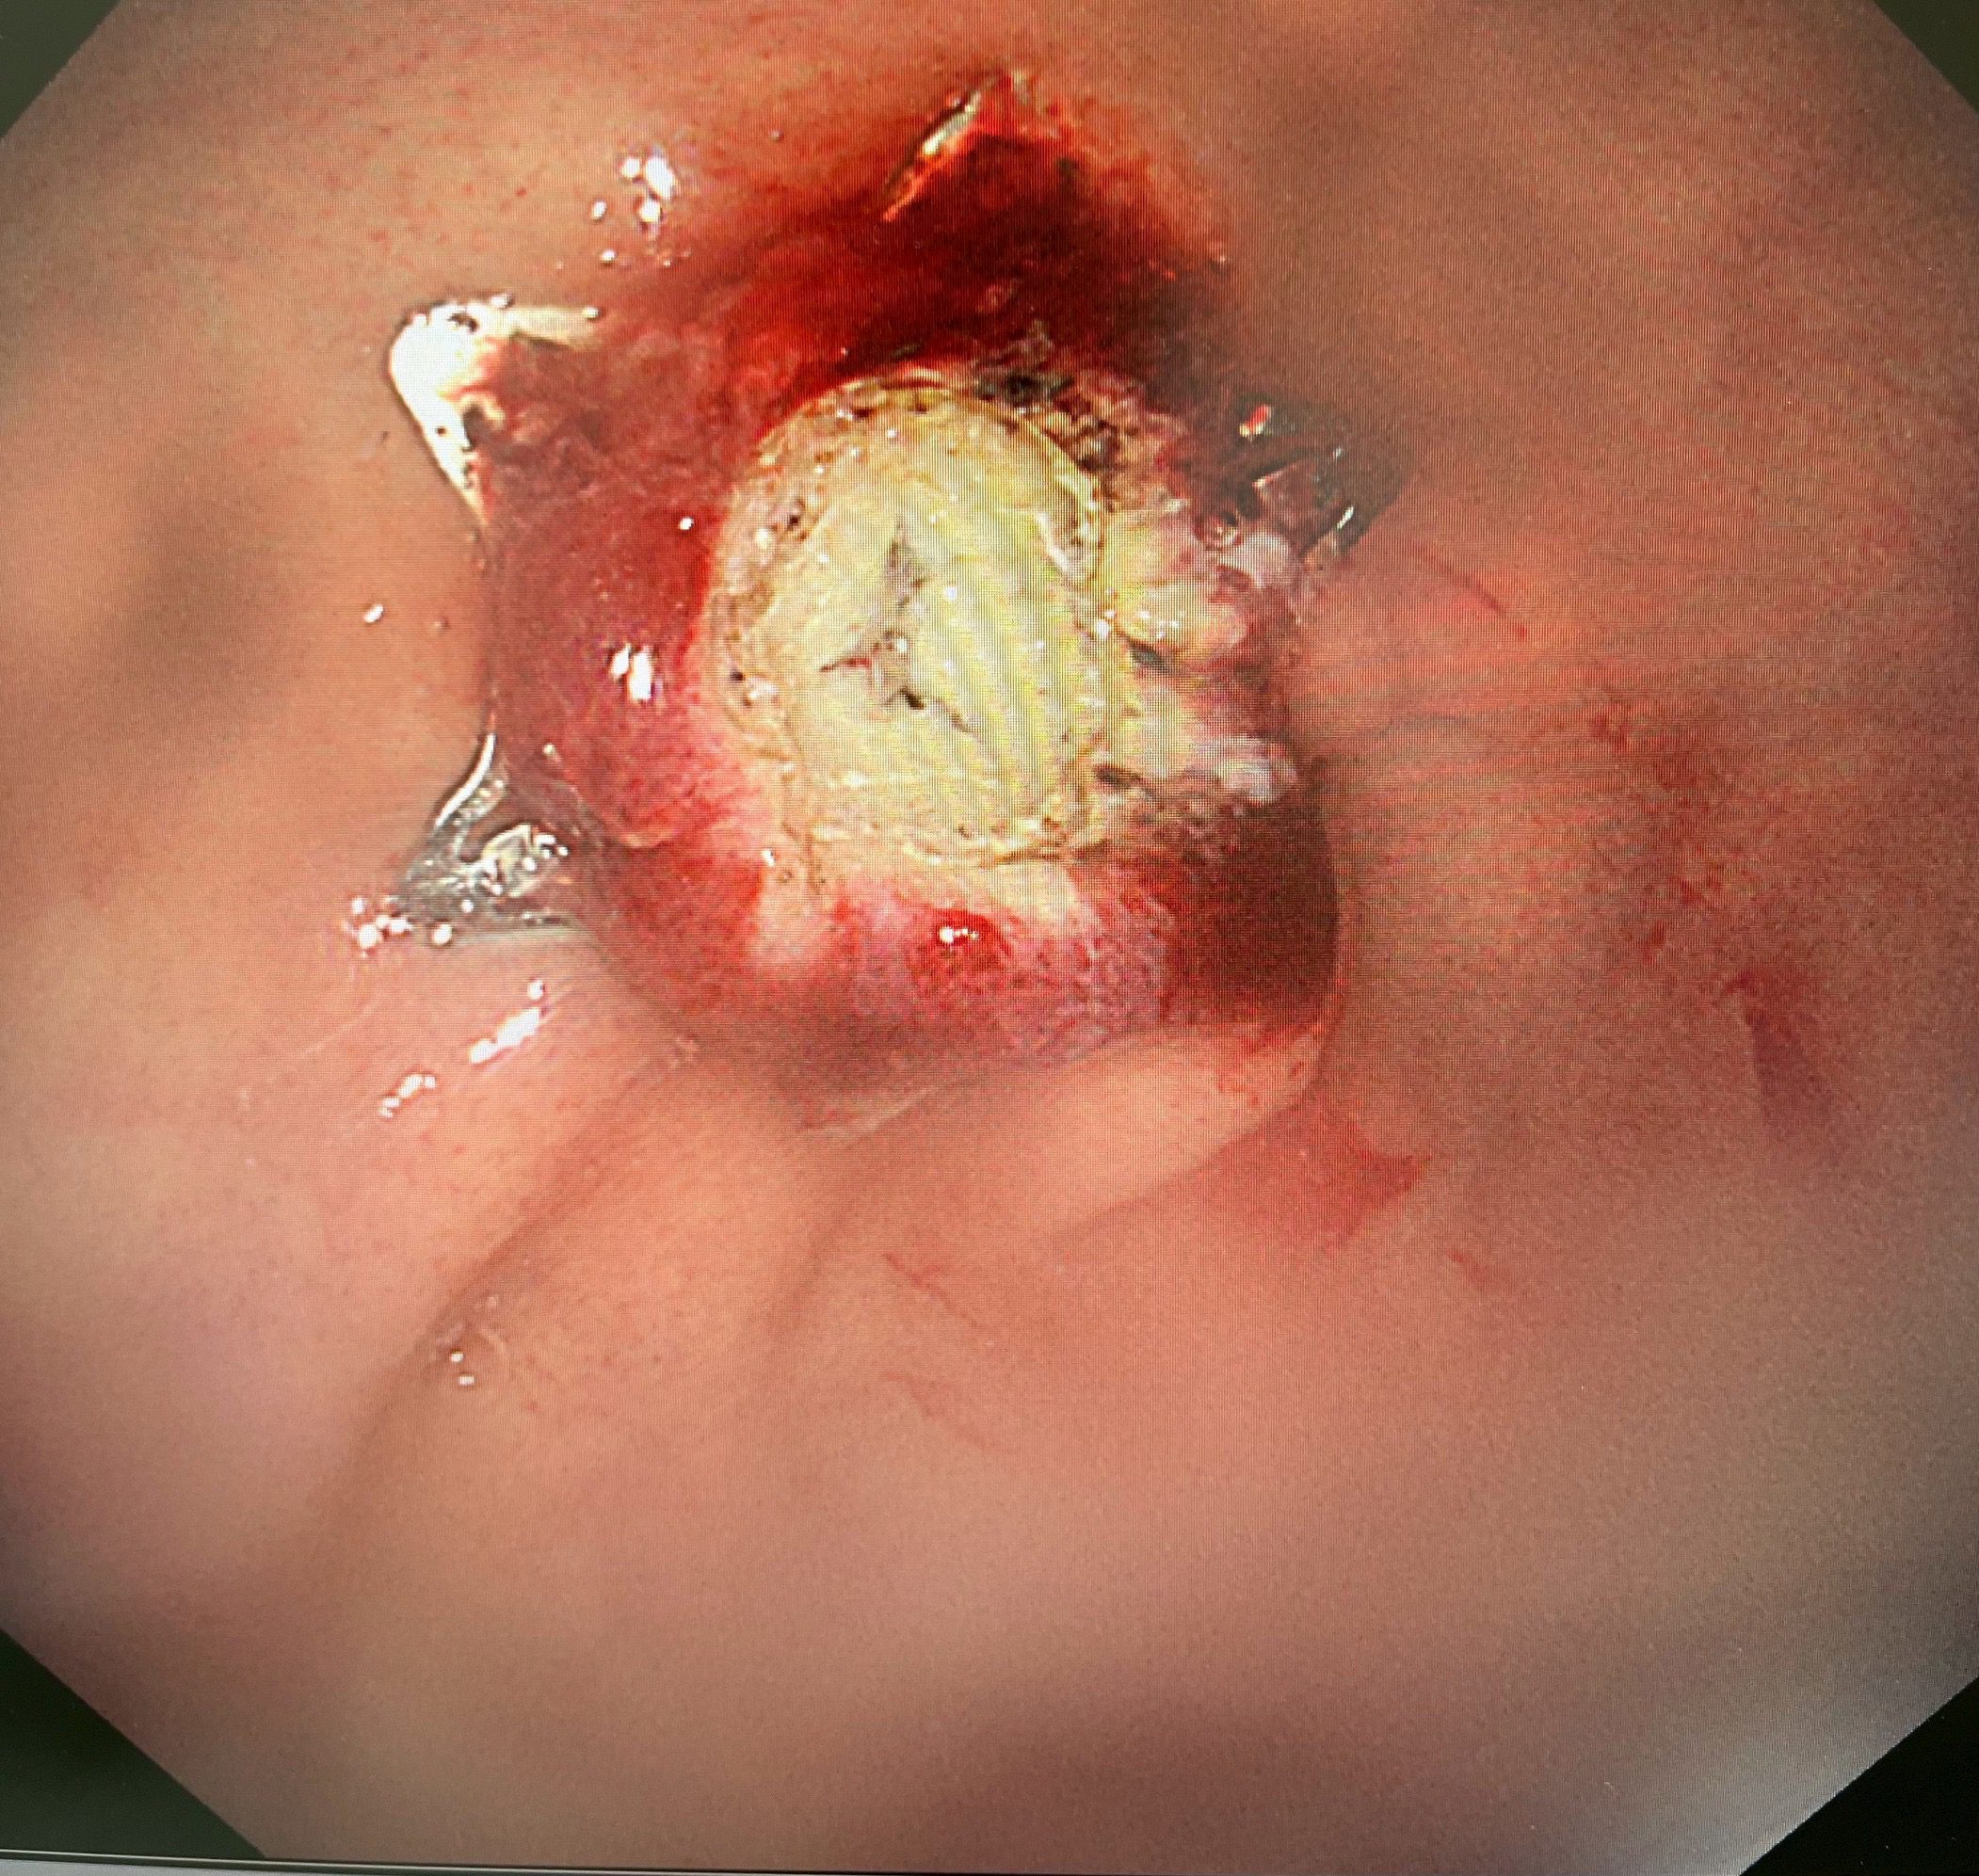

陳鴻運醫師採用新式的「內視鏡全層切除術」(EFTR)配合「pad lock clip closure device」閉合器械,僅花了25分鐘就成功將腫瘤完整切除(En Bloc resection)。這種技術能夠完整切除胃壁全層的病變,同時使用特殊夾具迅速閉合創口,避免胃內容物外漏導致腹膜炎等併發症。

「手術過程非常順利」,陳鴻運醫師描述:「我們透過內視鏡直視下將腫瘤完整切除,並立即使用pad lock clip閉合裝置關閉胃壁缺損。患者麻醉醒後完全沒有任何不適,沒有腹痛、腹脹等症狀。」

最令人驚喜的是患者的恢復情況。傳統手術後患者通常需要禁食數天,等待腸胃功能恢復,而這項新技術讓患者在術後12小時就開始進食流質食物,第二天已能進食軟質食物且無任何不適,隨即出院返家。